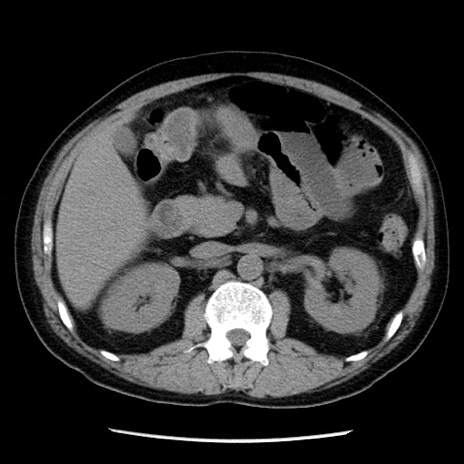

症例29(横断像)

【症例】40歳代男性

【現病歴】2日前から胃痛あり。徐々に周期的な激痛に変化した。本日になっても激痛があるため受診。

【身体所見】意識清明、BT 38-39℃台あり、腹部:膨満、やや硬、右下腹部に圧痛あり。

【データ】WBC 8500、CRP 23.26